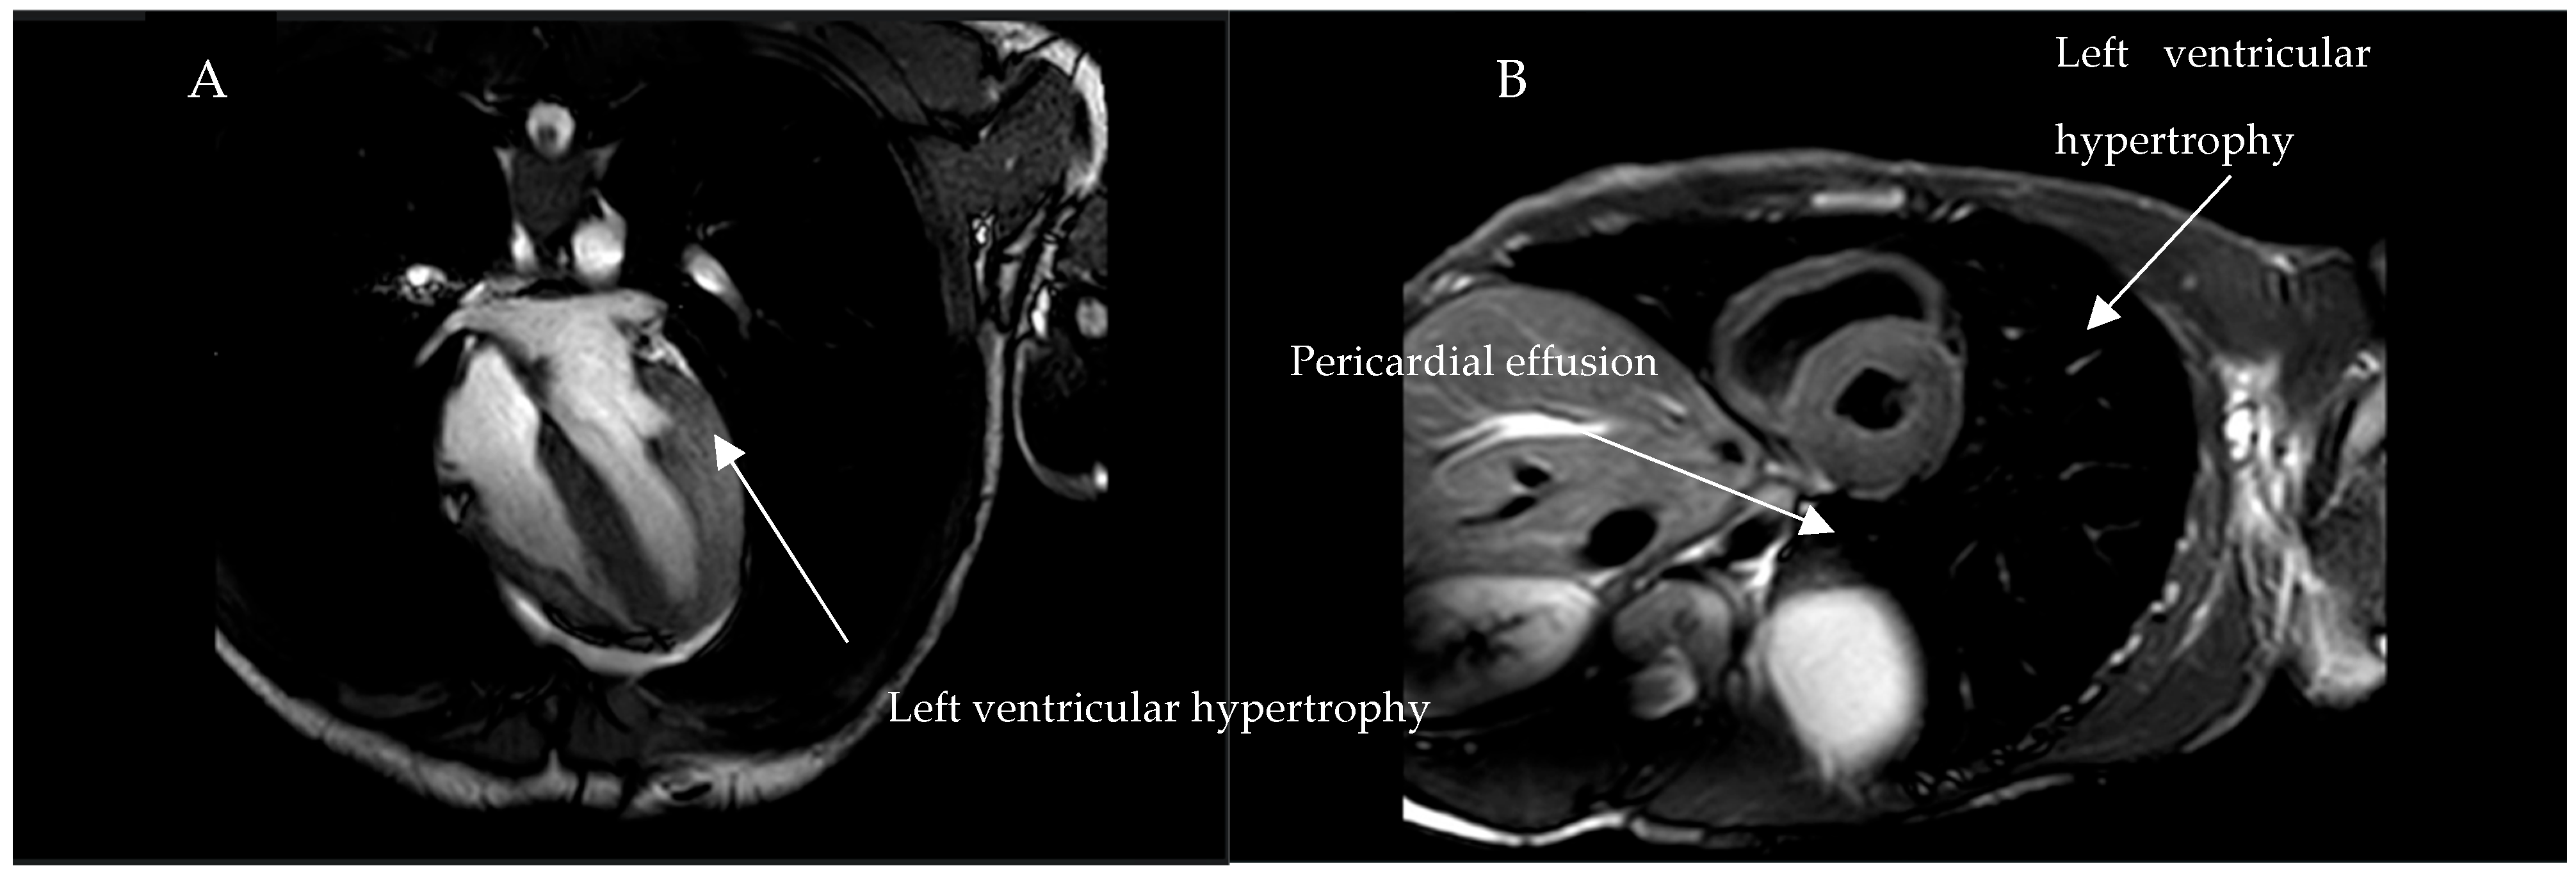

| 1 | F/54 | + | + | + | + | − | + | Periumbilical angiokeratomas |

| 2 | M/15 | + | + | − | + | − | + | Abdominal muscle pains |